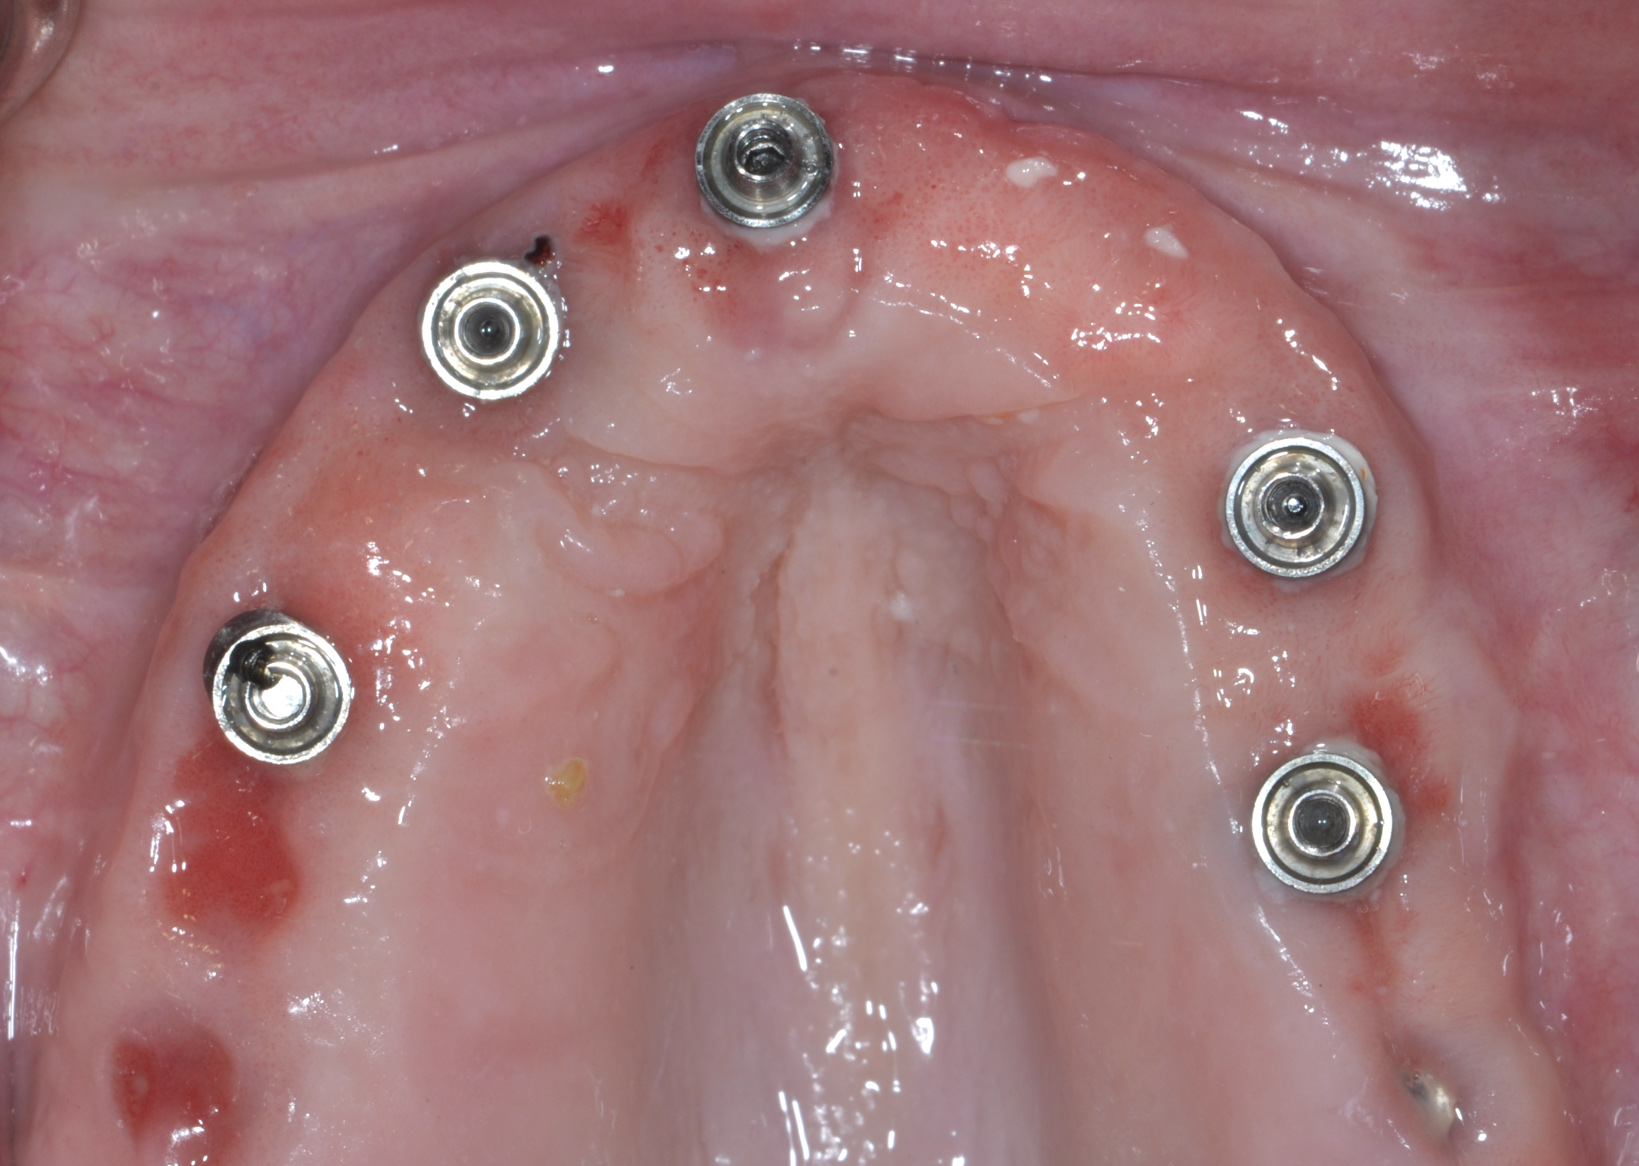

Fig 2. Upon removal of the prosthesis, plaque and debris were noted around the multi-unit abutments. Peri-implant mucositis was diagnosed.

Fig 3. Nonsurgical peri-implant treatment was performed, and the existing prosthesis was modified to enable access for patient-administered oral hygiene.

Fig 4. Four weeks after treatment, the patient presented with healthy peri-implant tissues.